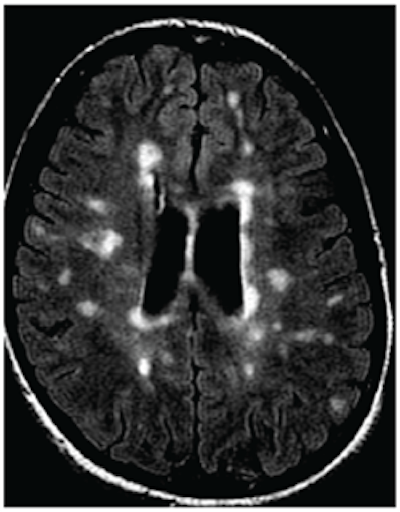

MRI of a person with multiple sclerosis. White areas show permanent scarring caused by the disease. Image courtesy of the University of British Columbia.The study presented at SIR 2017 was also led by Traboulsee and included 104 patients. All patients had a catheter inserted into their blocked veins, but only 49 underwent venoplasty, in which their vessel walls were expanded by a small inflated balloon. The study was double-blinded: Neither patients nor the physicians treating them knew who received the actual procedure. The researchers used MRI to evaluate the results.